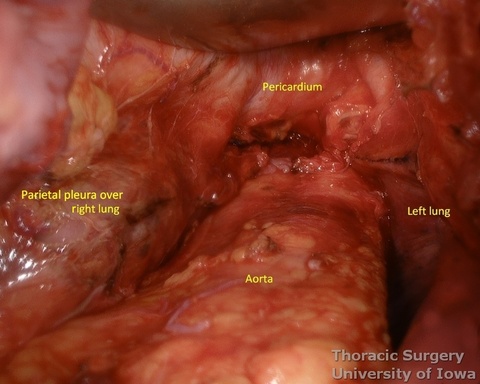

- The illuminated transhiatal retractor is advanced into posterior mediastinum under direct vision

- The distal thoracic esophagus is visualized.

- Esophagus is circumferentially mobilized under direct vision using combination of sharp and blunt dissection up to the level of the carina.

- Right lateral esophageal “ligament” (attachments to the parietale pleura, pulmonary ligaments and branches of vagal nerves) is exposed are divided under direct vision

- Left lateral esophageal attachments (“ligament") is divided under direct vision

- Aorto-pleural and aorto-esophageal ligaments divide posterior mediastinum into peri-esophageal and peri-aortic (thoracic duct and azygos vein) compartments. They may be distinctly seen in some patients.

- Esophageal arteries (aorto-esophageal branches) and vagal nerves are divided under direct vision using the energy device.

- Periesophageal and subcarinal lymph nodes are dissected separately or en-block with the esophagus under direct vision.

- Dissection of the distal and mid esophagus is completed using a combination of an energy device and suction tips.